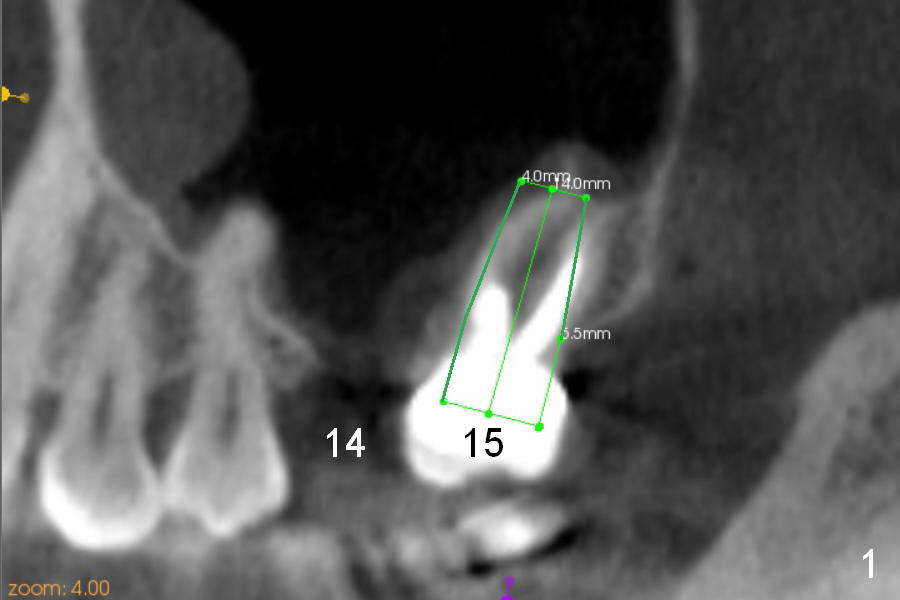

After immediate implant at the site of #19, pain is getting worse at #15 (Fig.1 CT sagittal section). The patient requests extraction, although the etiology of the pain remains unknown. The tooth #14 has been missing 13 years. The tooth #15 has tilted mesially. If an immediate implant is placed along the long axis of the tooth, it is 14 mm long (Fig.1). When the axis is changed according to the opposing dentition (Fig.2), the implant could be 3 mm shorter.